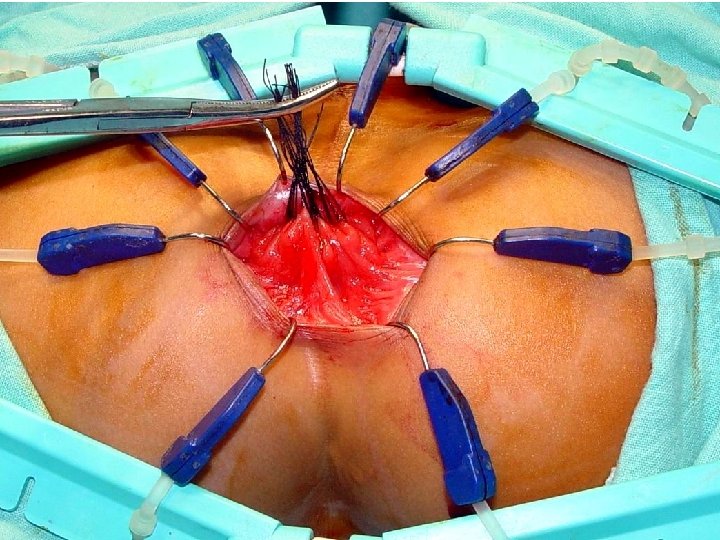

Treatment • Recently, one-stage pull-through with laparoscopic techniques. • More recently, a transanal endorectal pullthrough operation performed without opening the abdomen has been used with excellent results in rectosigmoid type

Operations • Swenson Procedure Resection of the aganglionic segment deep into the pelvis and direct end to- end anastomosis of the proximal colon to the anorectal canal. • Duhamel Procedure Aganglionic rectum is retained and the ganglionated bowel brought posteriorly and anastomosed to the aganglionic remnant in a side-to side

Operations Soave Procedure • The Soave with its variations, is the most frequently performed procedure in the world • It involves an extramucosal resection of a retained • aganglionic rectal segment. • The rectal mucosa is removed and a muscular cuff retained. • The ganglionated colon is brought through this cuff and anastomosed to the dentate line in the rectum, • Its variant is laparscopic assisted and endorectal pull through